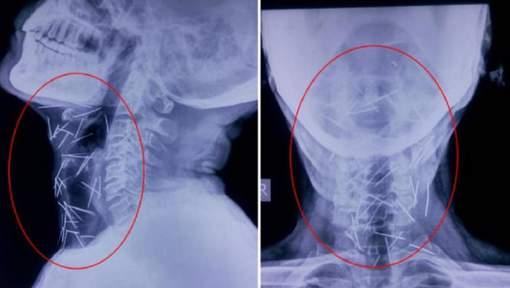

Un bărbat din India i-a uimit pe medici după ce aceștia au desoperit în radiografiile acestuia 75 de ace infipte în diverse părți ale corpului pacientului.

Din cele 75 de ace, 40 se află înfipte în gâtul bărbatului, 25 în piciorul drept și în ambele mâini.

Medicii spun că niciun ac nu a afectat vreun organ intern al pacientului.